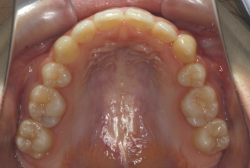

「歯並びの凸凹を直したい」という主訴で来院したケースです。診断の結果、たしかに「叢生」という隙間が足りないと言うことが原因の凸凹症例でした。

しかし、それ以上に問題なのは「前歯の噛み合い方が深すぎる」という症状で、初診の歯の正面写真を見ると下の前歯が全く見えません。こういう症状を矯正学では「過蓋咬合(かがいこうごう)」と言います。過蓋咬合を放置すると、将来的に顎関節に悪影響を与えるとされており、顎関節症の原因因子の一つです。また下の前歯の先端が、上の前歯の裏側の歯茎と強く接触するため、歯周病の原因にもなります。

検査の結果、凸凹が軽症なため非抜歯で矯正すること可能と判断、マルチブラケット装置にて治療しました。治療後は歯並びが綺麗になっただけでなく、噛み合わせ的にも正しい状態が確立しています。